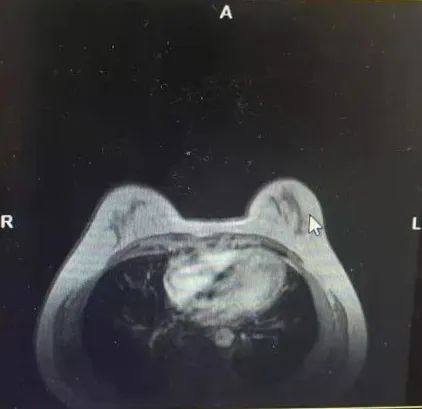

·乳腺核磁共振(MRI)

1、双侧乳腺呈多量型(ACR-c型);

2、右乳上方结节影,考虑为乳腺癌,BIRADS 6类,右乳外上结节及小片状强化灶,BIRADS 4a类,DCIS待排除;

3、双侧乳腺增生,BIRADS 2类。

图3乳腺MRI结果